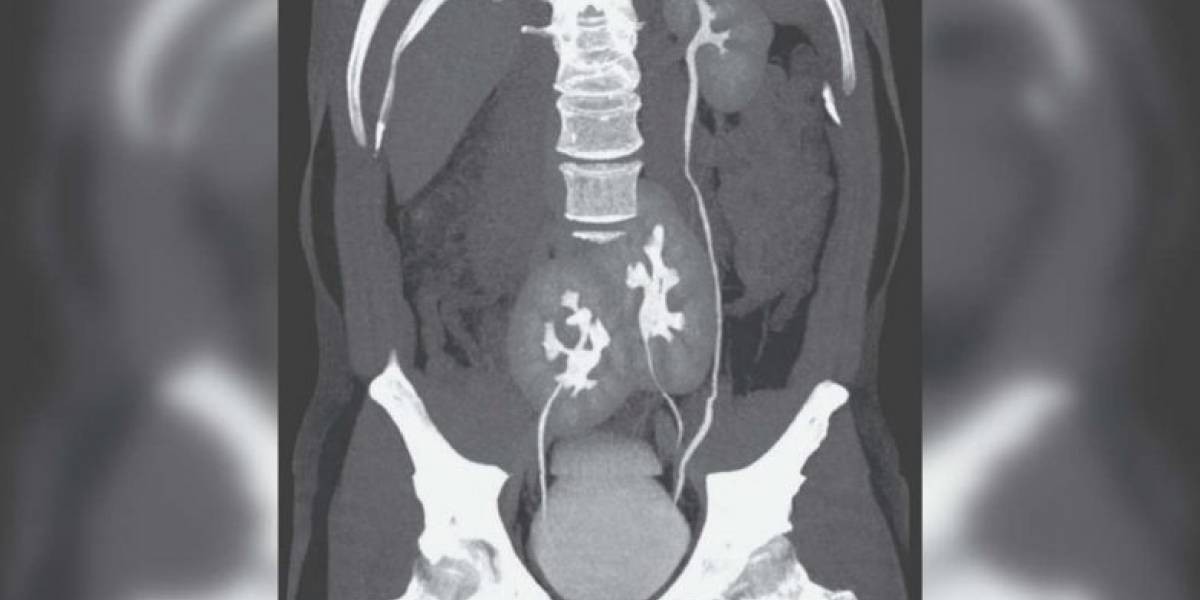

Las sospechas del equipo médico cuando el hombre contó los síntomas, apuntaban a una hernia discal, en la columna vertebral. Los médicos le pidieron una Tomografía Axial Computarizada (TAC), e hicieron el hallazgo.

Los médicos determinaron que la función renal del hombre es totalmente normal. "Tiene un riñón normal en el lado izquierdo y otro atrofiado y doble en el lado derecho", agregó el informe de la revista especializada.

Los médicos consideran que se trató de una malformación ocurrida durante el proceso embrionario, y no había sido descubierta porque los riñones, aunque son tres, trabajan perfectamente.